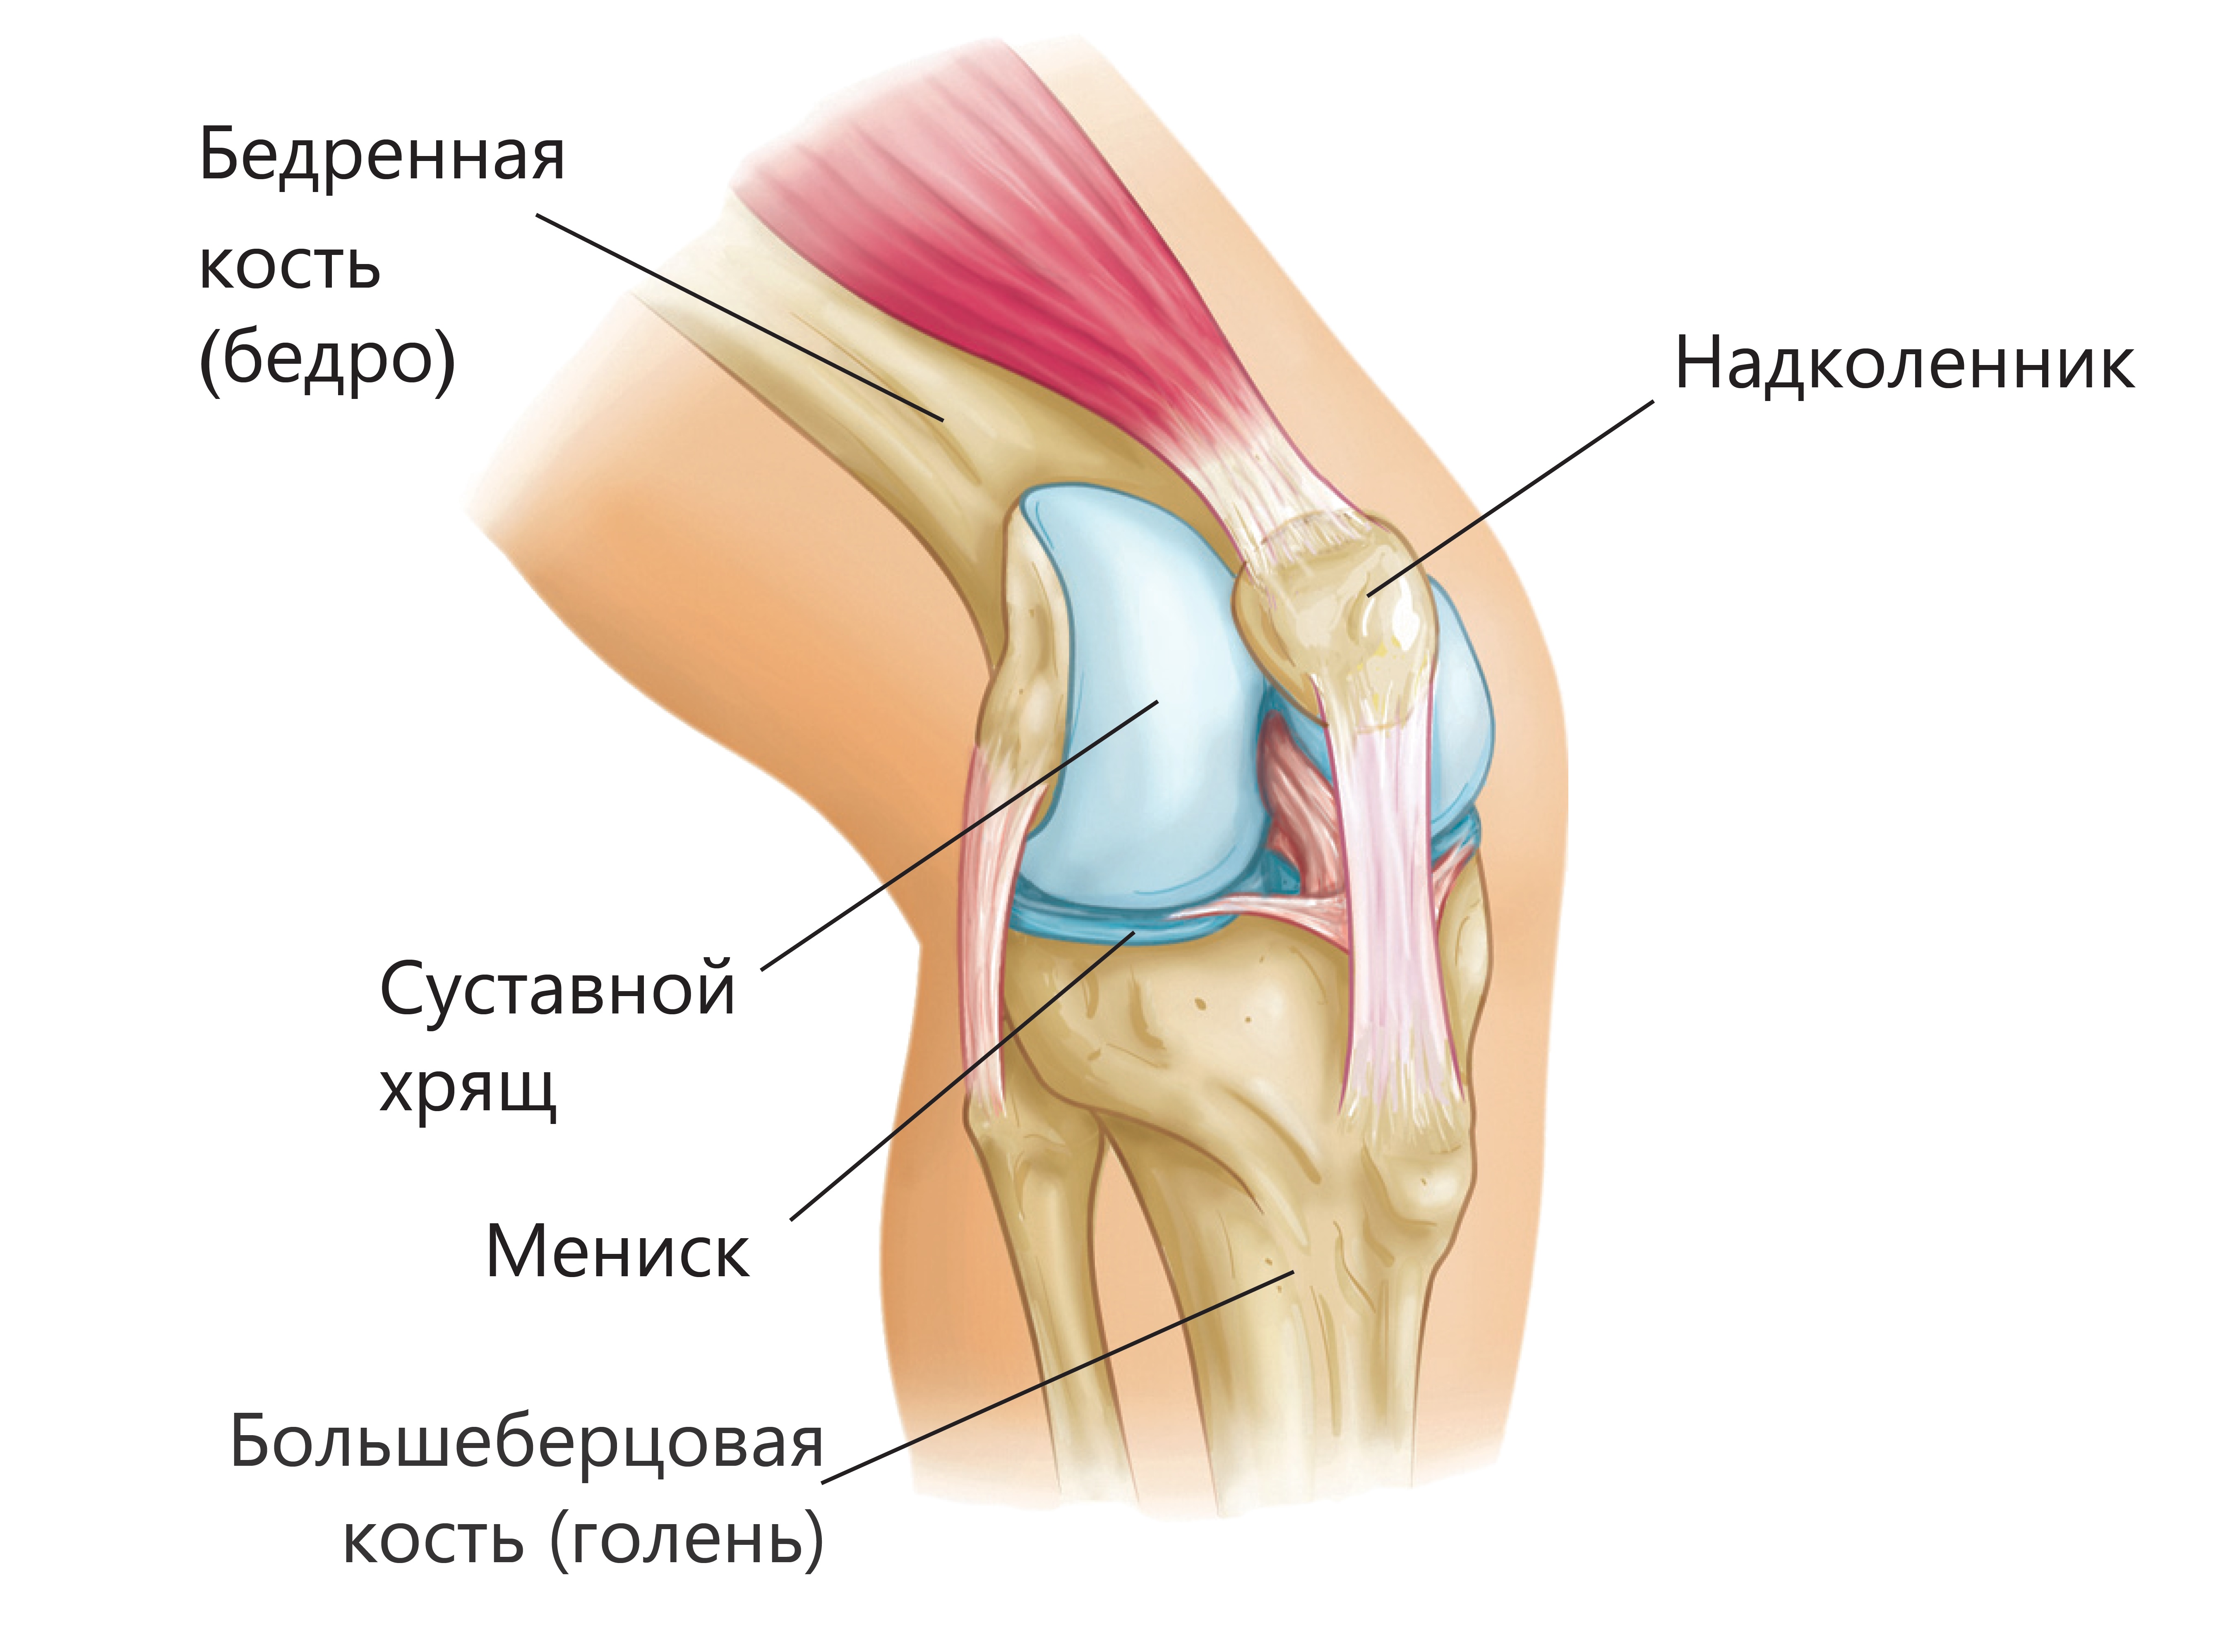

Анатомические изображения менисков и коленного сустава

Раздел: Иллюстрированные советы